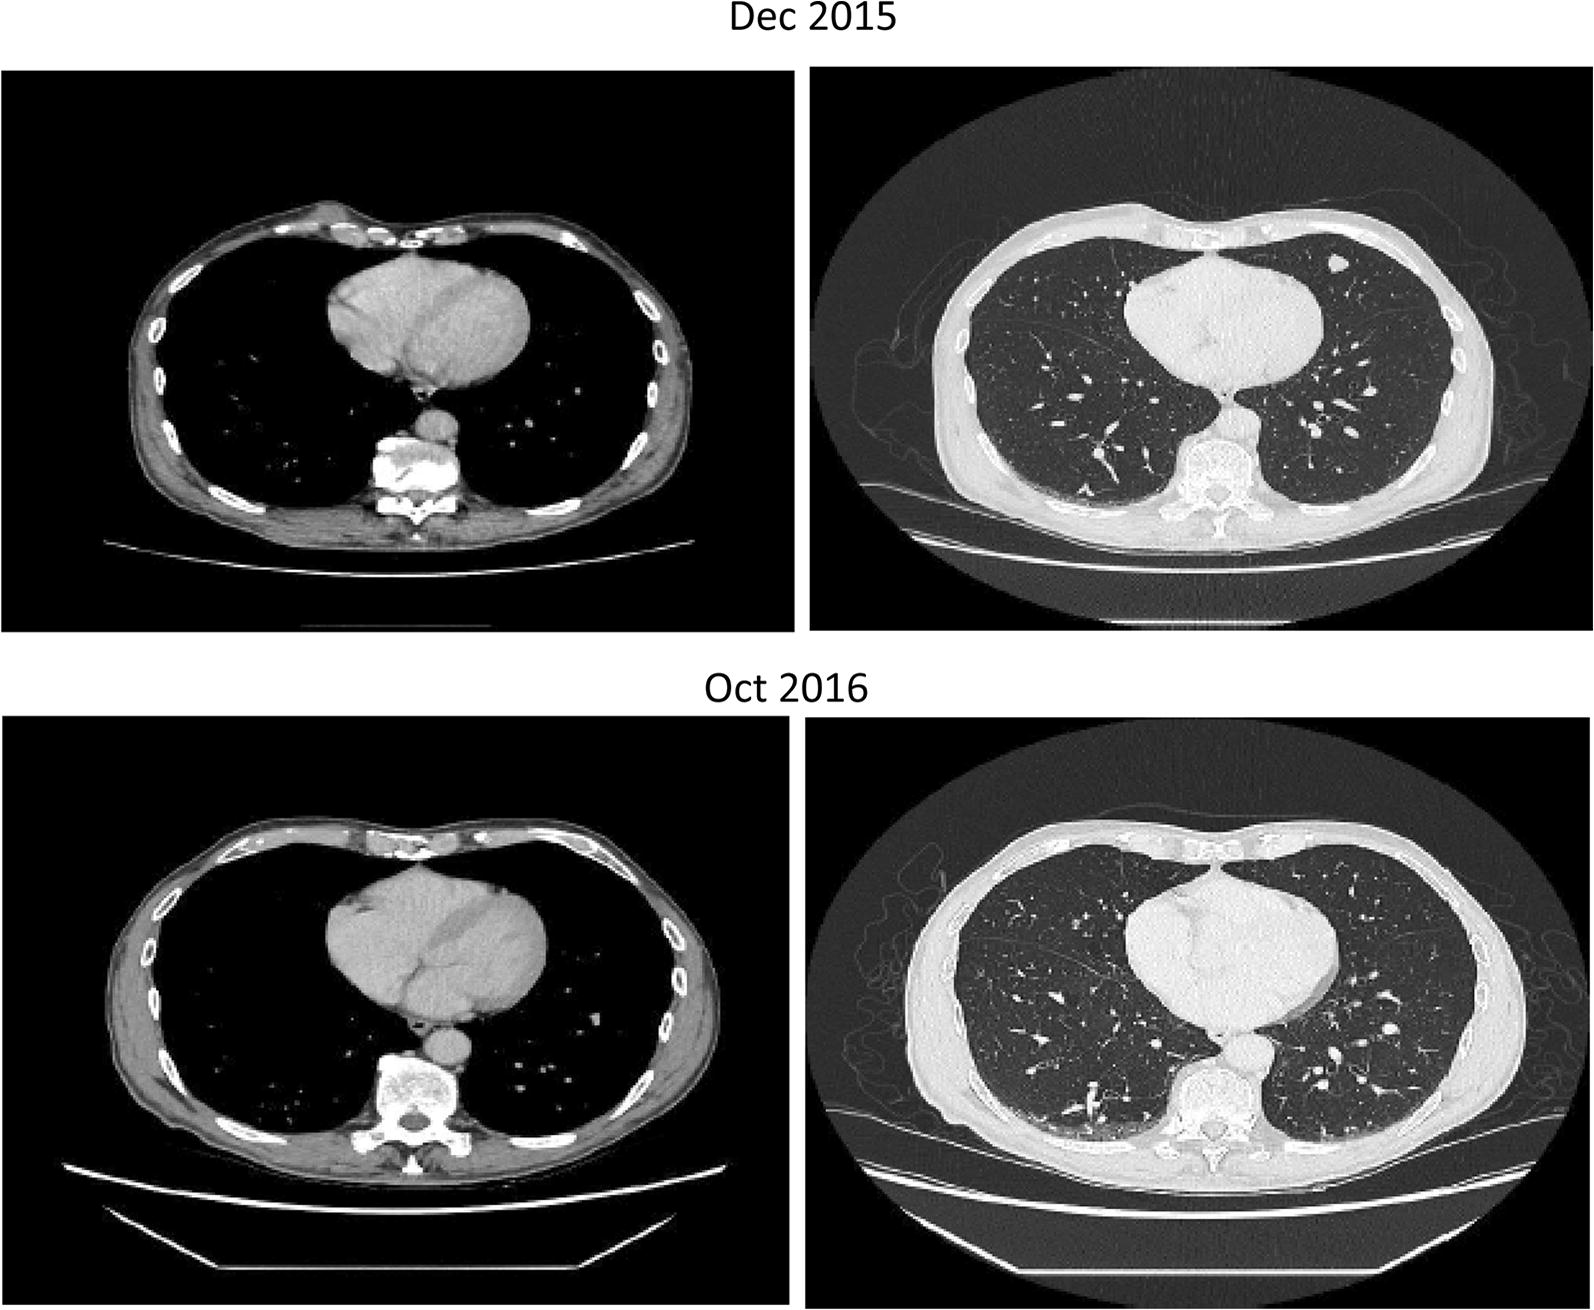

Patient 3

A 79 year-old male presented in 2014 with a melanoma on his left cheek (BT 2.4 mm, not ulcerated, BRAF wild-type) with a positive SNB leading to left neck dissection at time of diagnosis (no further positive nodes). Within months he developed paracardiac nodes, adrenal, lung and multiple large subcutaneous metastatic deposits. In view of his age and performance status he was commenced on IMM-101 on a named-patient program with initial stabilisation of disease. Upon progression of the subcutaneous disease he stopped IMM-101 and started with pembrolizumab, which showed a very rapid benefit as the subcutaneous lesions started to shrink within 4 days of the first infusion (Fig. 2). All visceral disease had also responded as seen on a restaging CT scan performed 6 weeks later with a PR > 50% as per RECIST1.1 criteria initially followed by a CR a few months afterwards (Fig. 3) upon continuation of pembrolizumab which lasted for 18 months and is still ongoing.

Fig. 3.

Complete reponse observed in a 79 year-old male with stage IV melanoma treated with IMM-101 followed by pembrolizumab (lung disease)

In the above mentioned preclinical studies IMM-101 has shown to stimulate an immune response suppressed by the underlying tumour, which may enhance responses to other modalities of treatment. Altogether 11 patients with metastatic melanoma have been treated with IMM-101 and CPIs either sequentially or concomitantly. Despite the majority of these patients were previously pre-treated, about the half of them experienced some kind of benefit. Four of them had an exceptionally good and rapid response and have been presented here. The CR rate with ipilimumab in melanoma is less than 3%. We reported 2 cases that had both received prior IMM-101 treatment and experienced a very good response with ipilimumab; one CR which lasted for a couple of years until unexpected trauma and the other with no new disease for 5 years. Although the CR for PD-1 inhibitors is higher, complete responses may take months before they become manifest. Here we presented a case of widespread stage IV M1c disease that had, following prior IMM-101 treatment, an objective response observed 4 days after the first infusion with the anti-PD1 antibody pembrolizumab and another case of a rapid complete response to treatment when IMM-101 was given in combination with the anti-PD1 antibody nivolumab.